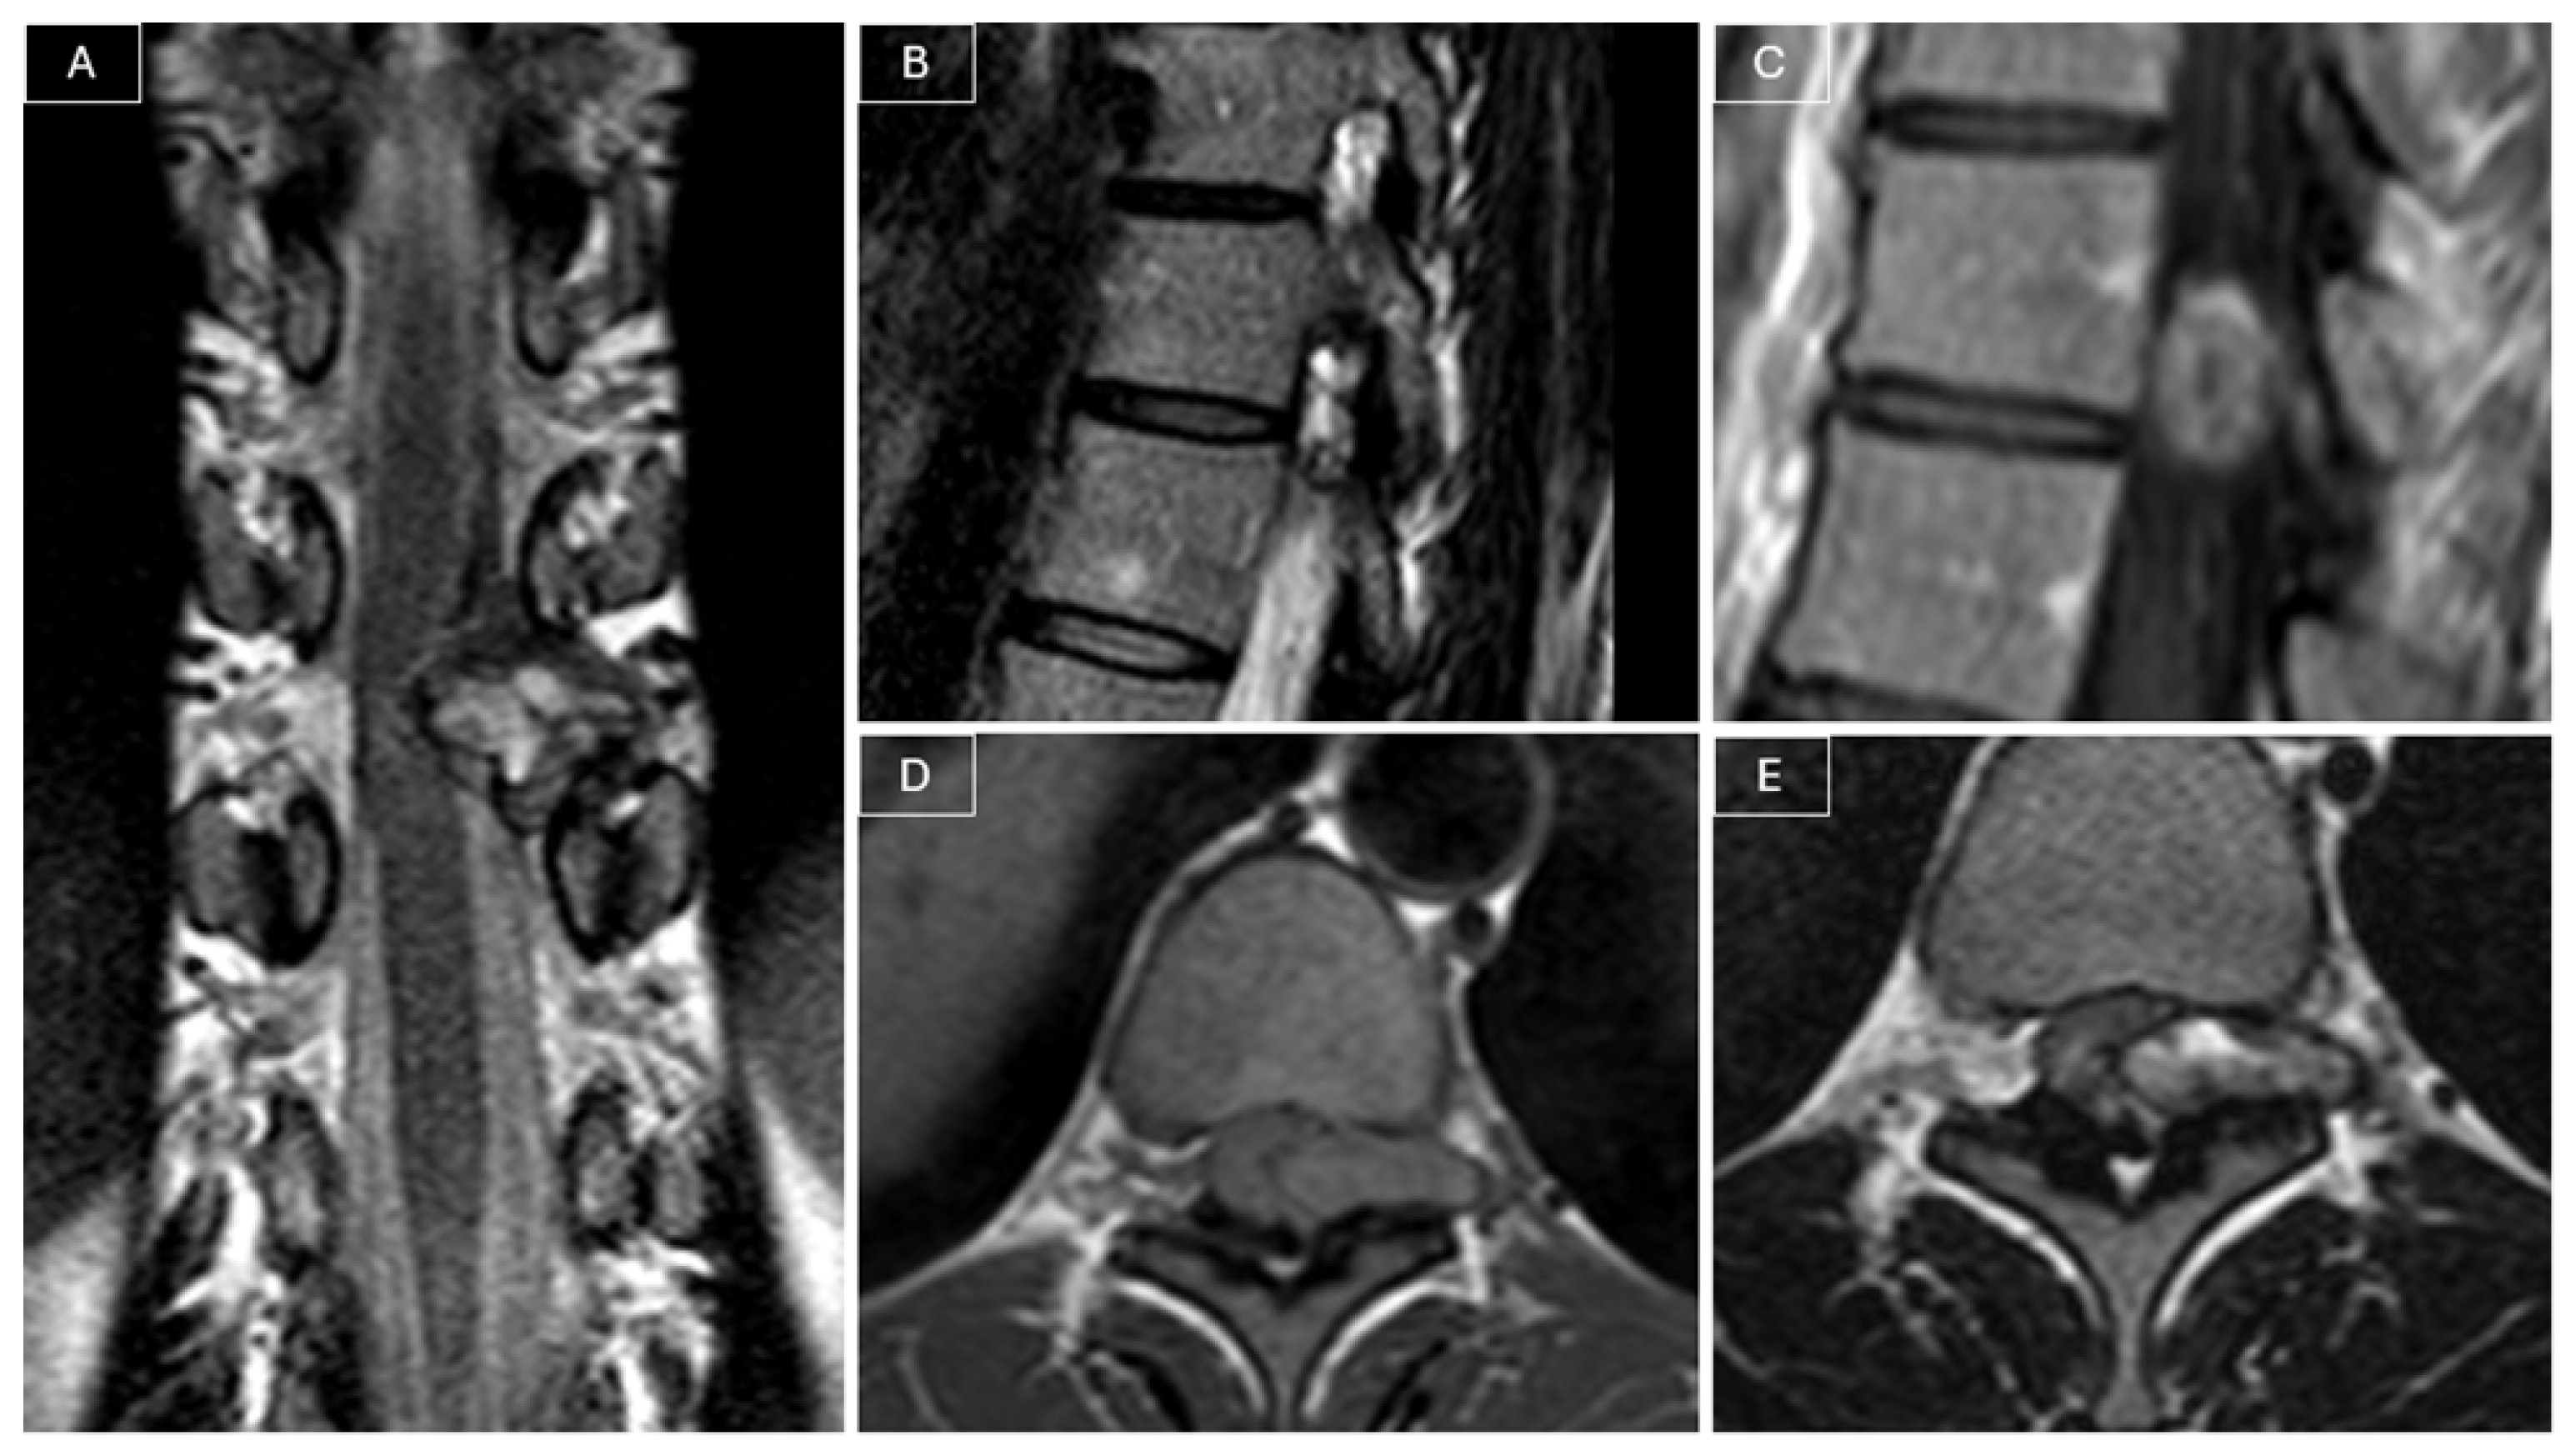

Radiological surveillance was performed at 2, 6, 12, and 18 months postoperatively with MRI. Follow-up MRI performed 18 months later revealed a recurrent lesion measuring 9 × 5 × 23 mm, in close contact with the spinal cord, associated with a T2 hyperintensity in the adjacent cord (see Figure 3).

Figure 3. MRI at 18-month follow-up revealed tumor recurrence. (A) Sagittal T2-weighted images showed a T2 hyperintensity in the adjacent cord. (B,C) Post-contrast T1-weighted images showed a nodular contrast-enhancing lesion in contact with the spinal cord, suspicious for tumor recurrence.